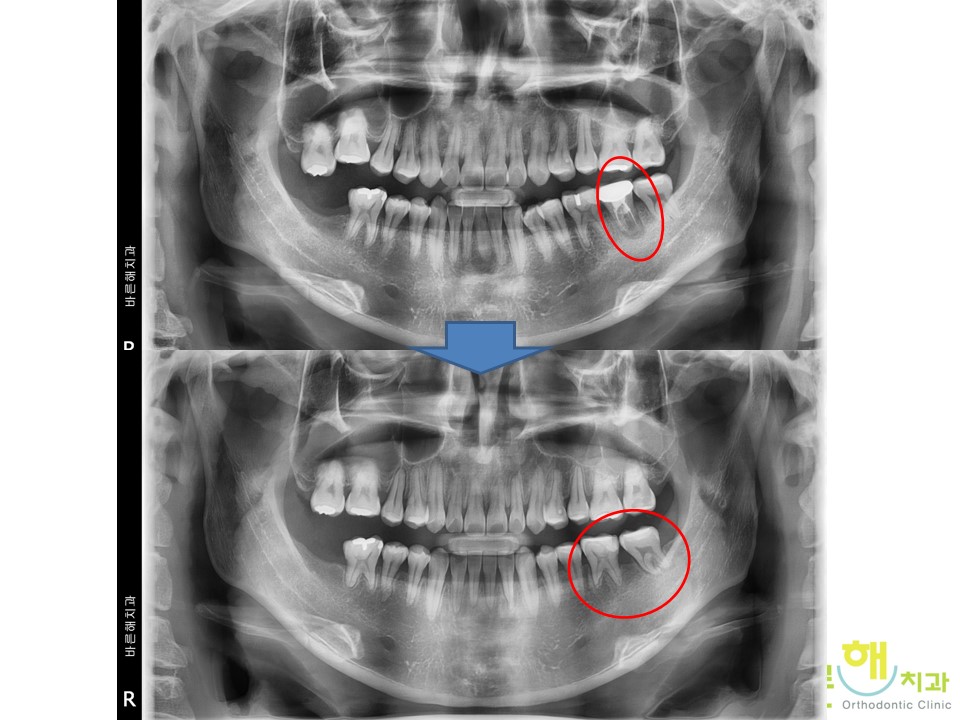

¿À¸¥ÂÊ ¾î±Ý´Ï°¡ À¯Âø(Ankylosis)ÀÌ ÀÖ¾î

¿òÁ÷ÀÌÁö ¸øÇÏ´Â °ÍÀÌ È®ÀεǾú½À´Ï´Ù.

¾î±Ý´Ï´Â Áß¿äÇÑ Ä¡¾Æ·Î ±³Á¤Ä¡·á½Ã¿¡

¿òÁ÷ÀÓÀÌ Àß Á¶ÀýµÇ¾ß ÇÏÁö¸¸

À¯Âø(Ankylosis)ÀÌ µÈ Ä¡¾ÆÀÇ °æ¿ì

¿òÁ÷ÀÏ ¼ö ¾ø±â ¶§¹®¿¡

Á¦¿ÜÇϰí

¸¶¹«¸® ±³Á¤Ä¡·á¸¦ ÁøÇàÇϱâ·Î

ÇÏ¿´½À´Ï´Ù.

»¡°£ µ¿±×¶ó¹Ìó·³ ½ÉÇÑ ÃæÄ¡·Î

»ì¸± ¼ö ¾ø´Â Ä¡¾Æ¸¦ »©°í

µÚ¿¡ ÀÖ´Â »ç¶û´Ï¸¦ ²ø¾î¿Í¼­

»ç¿ëÇÒ ¼ö ÀÖ°Ô ÇÏ¿´°í

¸¹Àº ¿òÁ÷ÀÓÀÌ ÀÖ¾ú

Áö¸¸

Ä¡¾Æ´Â °Ç°­ÇÑ »óÅ·Î

Àß Ä¡·áµÈ °ÍÀ» º¼ ¼ö ÀÖ½À´Ï´Ù.